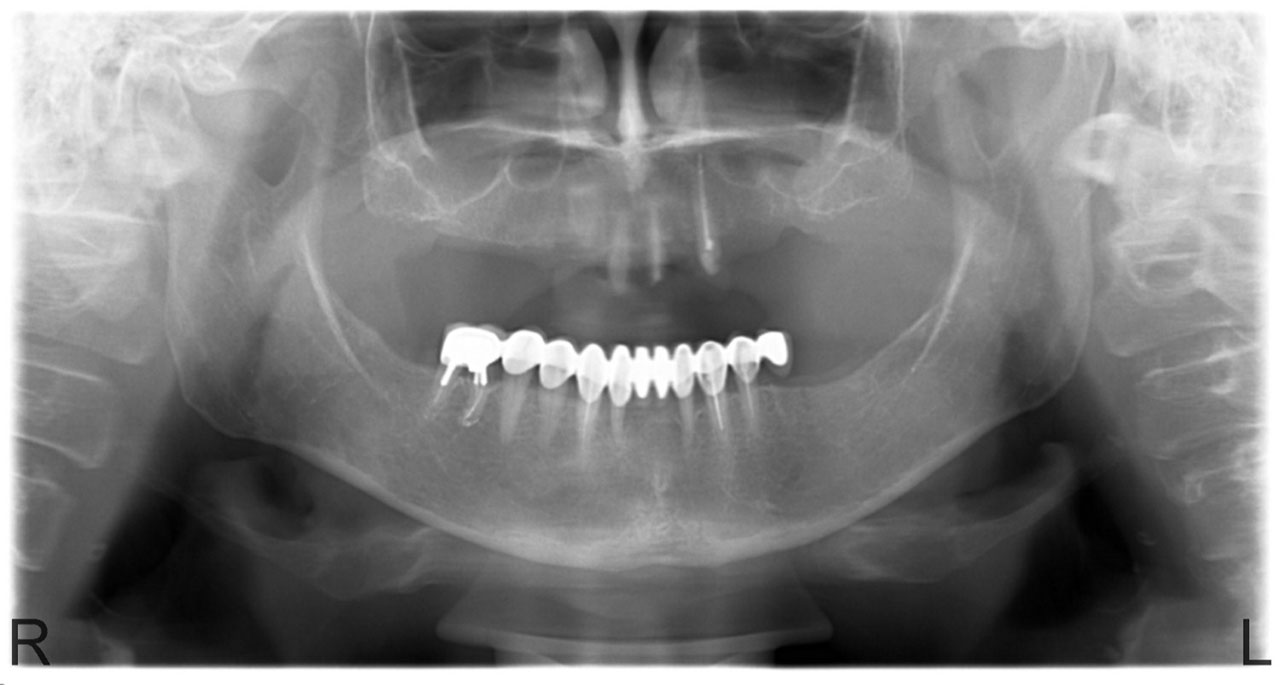

• esettanulmany-07

Teljes fogatlanság.